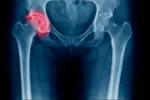

El déficit de vitamina D aumenta riesgo de fracturas

Mantener unos niveles adecuados de vitamina D favorece la salud ósea y contribuye a fijar el calcio en los huesos, mientras que un déficit de este micronutriente es un factor de riesgo para sufrir fracturas vertebrales, según han explicado los especialistas que han participado en el XV Encuentro Nacional de Salud y Medicina de la Mujer (SANEM15) celebrado en Madrid.